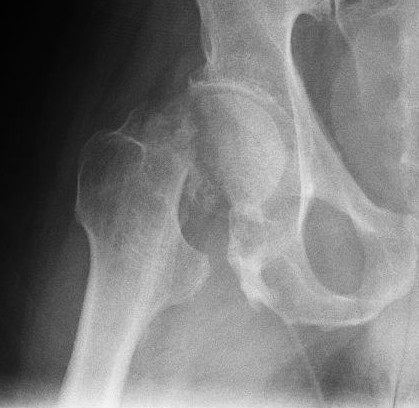

Radiograph of a hip joint showing a femoral neck fracture.